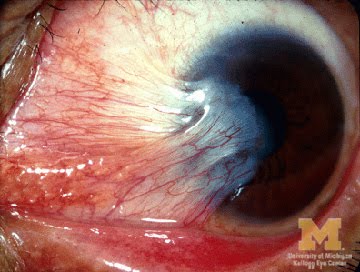

PTERYGIUM SURGERY

Pterygium Surgery - Page 2 | Pterygium Surgery - Page 3 | Pterygium Surgery - Page 4 | Pterygium Surgery - Page 5 | Pterygium Surgery - Page 6 | Pterygium Surgery - Page 7